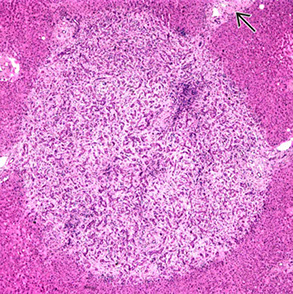

Adult Giant Cell Hepatitis

- aka postinfantile giant cell hepatitis or syncytial giant cell hepatitis

Pattern of injury that can be seen c multiple etiologies

-- infx suspected port-transplant and can cause progressive fibrosis

- may be linked to HHV-6A, CMV, HEV, EBV

- in HHV-6A the bile ducts can also have giant cell transformation

2 main categories of histologic findings

1) mod to marked giant cell transformation c mild to mod lymph inflam in portal tracts and lobules and lobular cholestasis

- is the classic form of adults giant cell hepatitis and should prompt the ddx of autoimmune hepatitis, drug effect and viral hepatitis

- can be seen c acute liver failure and progression of fibrosis (including cirrhosis)

2) can be seen in chronic HCV c mild but persistent giant cell transformation of zone 3 hepatocytes

- not assoc c inflam grade or fibrous stage, but usually seen on subsequent bx

- different causes of cholestasis can also cause giant cell change (term "giant cell transformation" may be preferred)

Giant cell hepatitis. Multinucleated giant cells seen along with Kupffer cell hyperplasia, suggestive of giant cell hepatitis.[3]